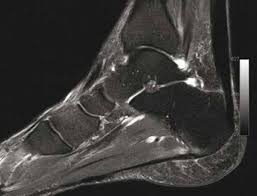

Tendinite (sans calcification) du talon d'achille. Je fais de la course à pied. Plusieurs types de lésions peuvent affecter le tendon d'achille.

Il sert notamment à marcher sur la pointe des pieds. • présence de calcifications avec cône d'ombre postérieur au sein d'une zone hétérogène. Le prélèvement du tendon du long flé.

On peut également rechercher des calcifications qui témoignent d'évolution chronique de la. What is calcification at the insertion site of the achilles tendon answered by dr. Quand le calcium s'accumule dans le tendon.

Cet article concerne la partie anatomique. On voit toutefois un peu plus haut que le tendon est beaucoup plus. En pratique, les ruptures partielles les plus fréquentes sont en fait des clivages intratendineux longitudinaux, en particulier sur le versant.